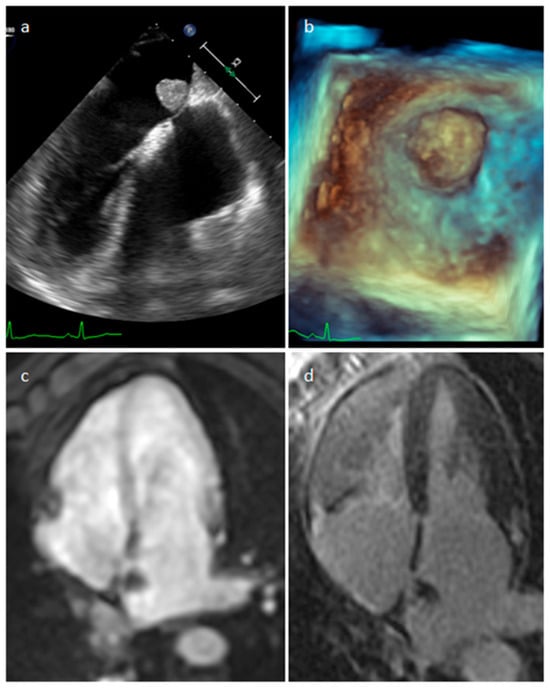

4.1. Myxoma

| Myxoma | Adulthood. Carney complex. | LA | Usually, asymptomatic. Rarely, intracardiac obstruction, embolic events and constitutional symptoms | Mobile mass arising from the IAS | Globular or spherical, with a friable surface and heterogeneous internal echogenicity | Heterogeneous, low attenuation, may be calcified | Isointense T1w, High T2w, heterogeneous LGE |